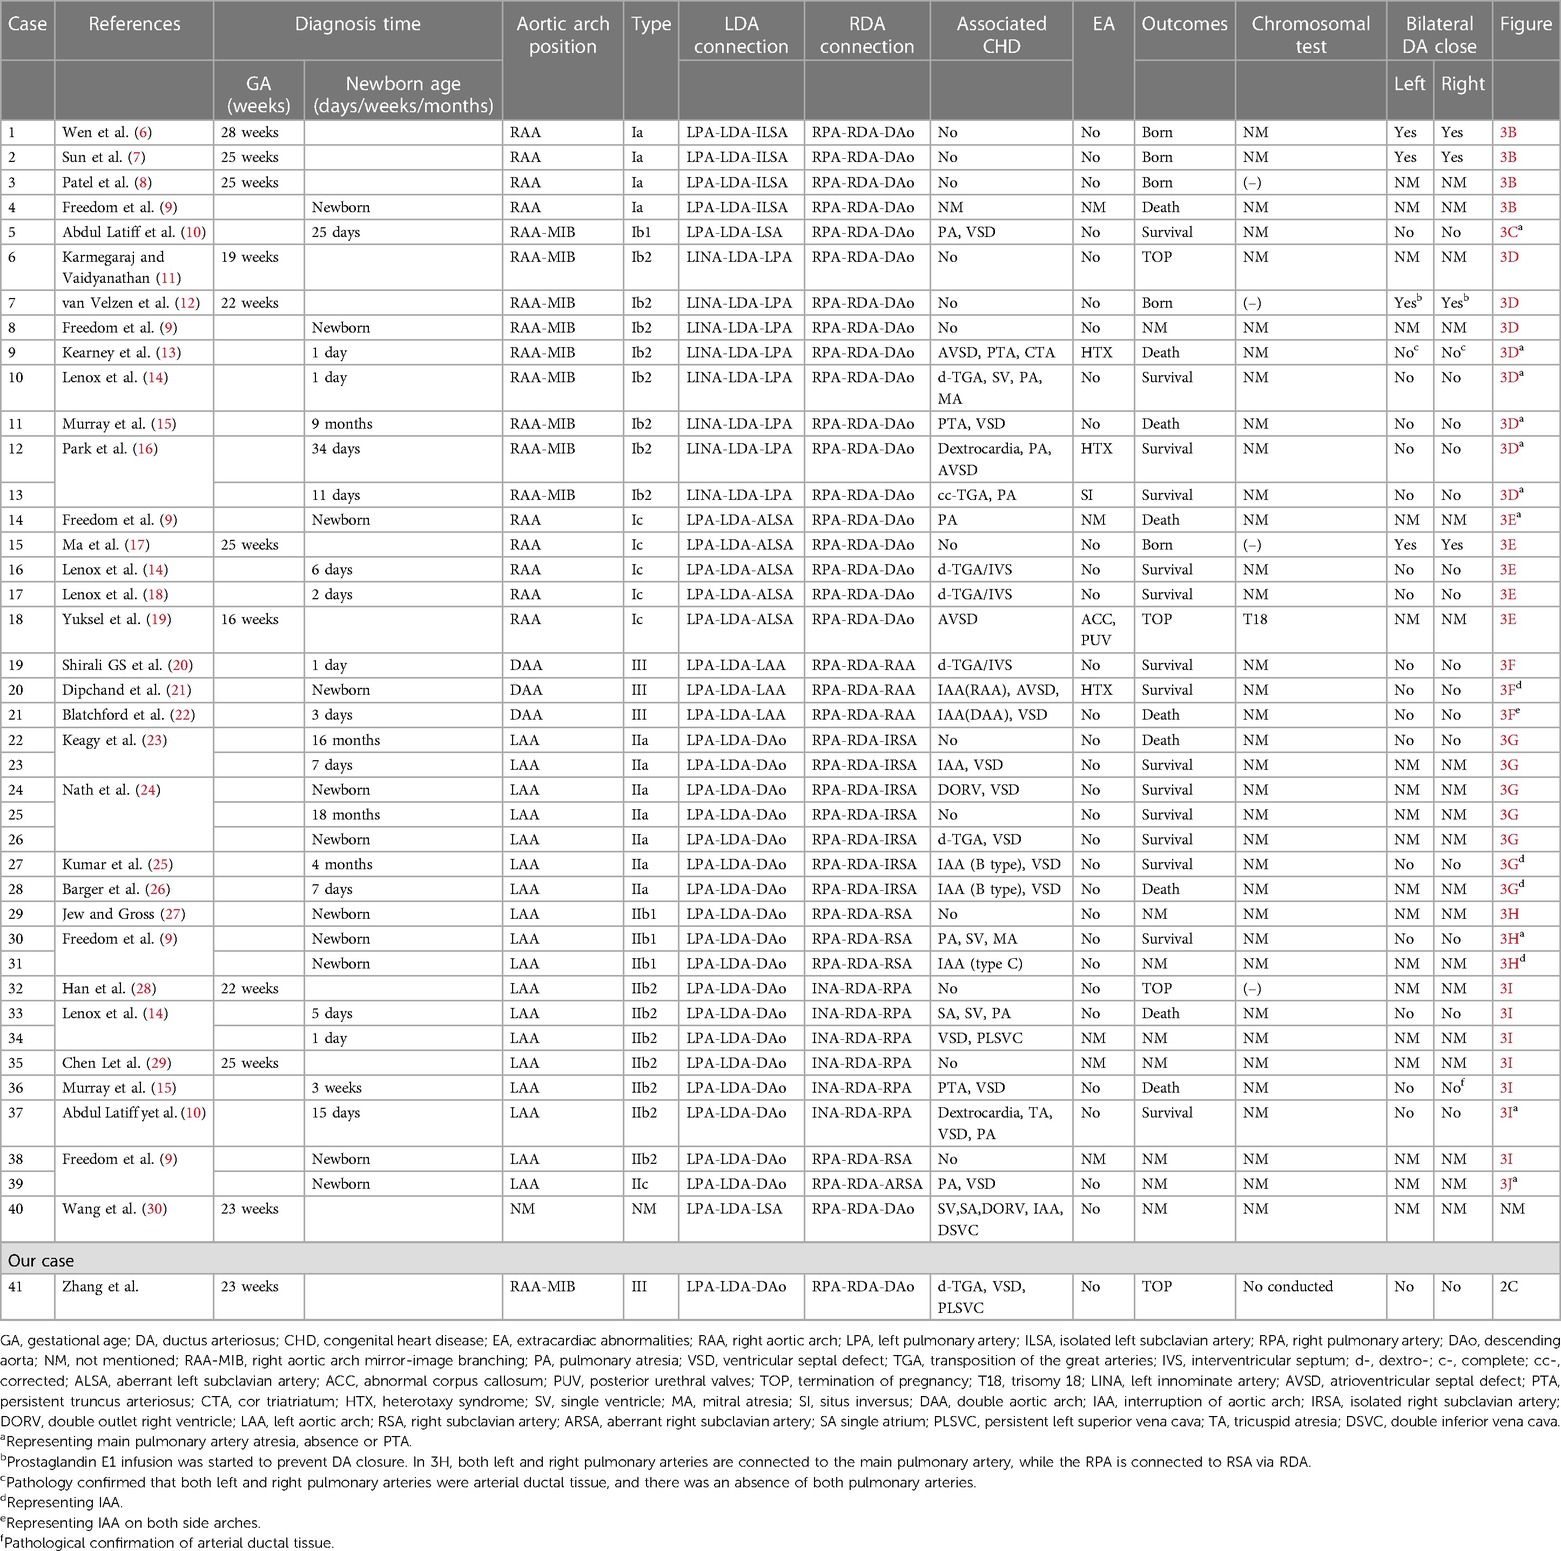

A 22-year-old female patient, Gravida 3, Para 2 (G3P2), underwent fetal echocardiography at 23 weeks of gestation. Both the two-dimensional (2D) grayscale image and color Doppler flow imaging (CDFI) revealed cardiac structural abnormalities. The 2D grayscale imaging showed that the main pulmonary artery (MPA) originated from the left ventricle (LV) and could be seen overriding the interventricular septum, with left and right blood vessels separating at the distal end (Figure 1A). Furthermore, the aorta (Ao) was shown to originate completely from the right ventricle (RV) (Figure 1B). The above signs indicated that the fetus had d-TGA combined with a ventricular septal defect (VSD). 2D grayscale combined with CDFI showed that the Ao was located on the right side of the trachea and that the first blood vessel originating from the Ao was the left innominate artery (LINA) (Figure 1C), which was toward the left shoulder of the fetus. Subsequently, the left common carotid artery (LCCA) and left subclavian artery (LSA) were separated (Figure 1D), indicating RAA-MIB (Supplementary Video S1). The following scan revealed a rare vascular ring, which extended from the confluent of the left pulmonary artery (LPA) and right pulmonary artery (RPA) to the left and right ductus arteriosus (LDA and RDA), converging into the descending aorta (DAo). Therefore, the BDA completely encircled the trachea, forming an “O”-shaped vascular ring (Figures 1E,F, Supplementary Video S1). In addition, a PLSVC was observed; the 2D grayscale longitudinal plane showed that this vessel converged into the coronary sinus (CS) (Figure 1G). We have provided a pattern diagram to help understand this case (Supplementary Figure S1).

Figure 1. Abnormal cardiac structure and vascular abnormalities in the fetus. (A,B) 2D grayscale images showing d-TGA combined with a VSD. (C,D) 2D grayscale combined with CDFI showing RAA-MIB. (E,F) 2D grayscale combined with CDFI showing BDA encircling the trachea. (G) 2D grayscale showing that the PLSVC converges into the CS.